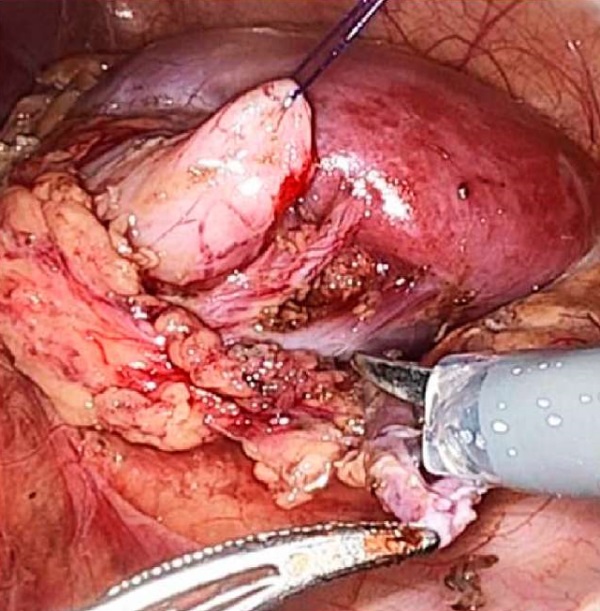

Введение. Обструкция пиелоуретерального сегмента (ОПУС) — самая частая причина хирургических вмешательств на верхних мочевых путях у детей. Нами проведён сравнительный анализ результатов применения робот-ассистированной лапароскопической пиелопластики (РАП) с использованием системы da Vinci Xi и традиционной лапароскопической пиелопластики (ЛП).

Материалы и методы. В исследование включены 40 пациентов, которым выполнена пиелопластика. Мы разделили пациентов на две группы: в группе 1 — 20 пациентов, которым выполнена РАП, в группе 2 — 20 пациентов, которым выполнена ЛП. Все операции выполнены одним хирургом.

Заключение. Сравнительный анализ эффективности и безопасности использования РАП и ЛП при ОПУС у детей демонстрирует сопоставимые результаты по длительности хирургии и динамике регрессии дилатации чашечно-лоханочной системы в послеоперационном периоде. В качестве преимущества РАП по сравнению с ЛП следует считать сохранение физических кондиций оператора на всём протяжении формирования анастомоза, позволяющих формировать анастомоз максимально прецизионно, избегая компромисса между желаемым качеством наложения интракорпорального шва и реальным результатом на фоне неизбежной физической усталости оператора при использовании лапароскопического доступа.